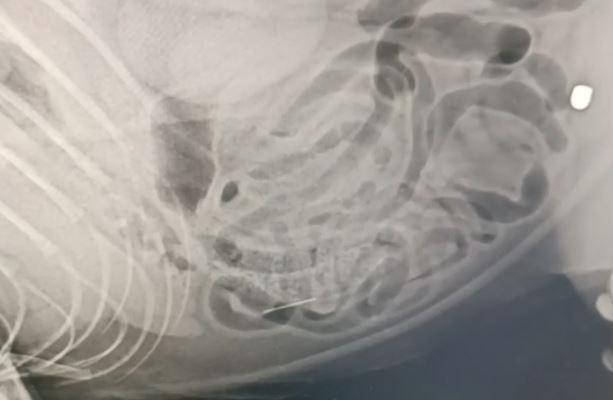

При обследовании ветеринары обнаружили в теле четвероногого пулю, застрявшую в бедре, и иглу в брюшной полости.